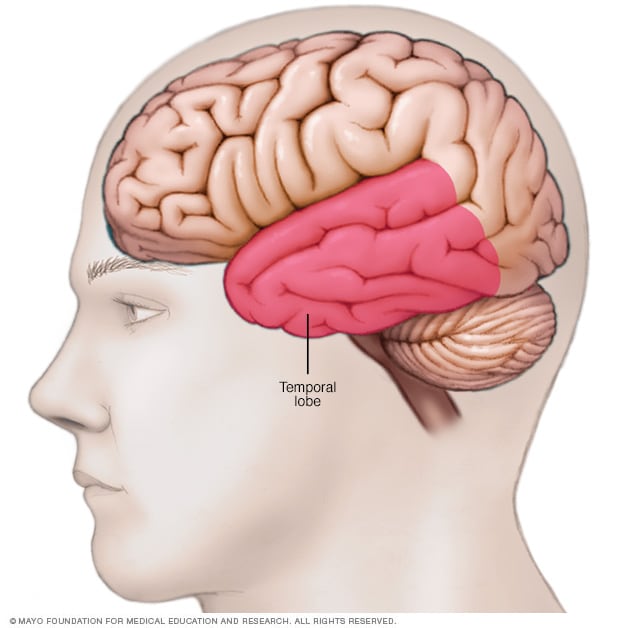

Location of temporal lobe

The temporal lobe is located along each side of the brain.

- Resective surgery. This surgery is the most common epilepsy surgery. With this surgery, the surgeon cuts out brain tissues in the area of the brain where seizures occur. The area may be the site of a tumor or brain injury. Resective surgery most often occurs on one of the temporal lobes. This area controls visual memory, language comprehension and emotions.